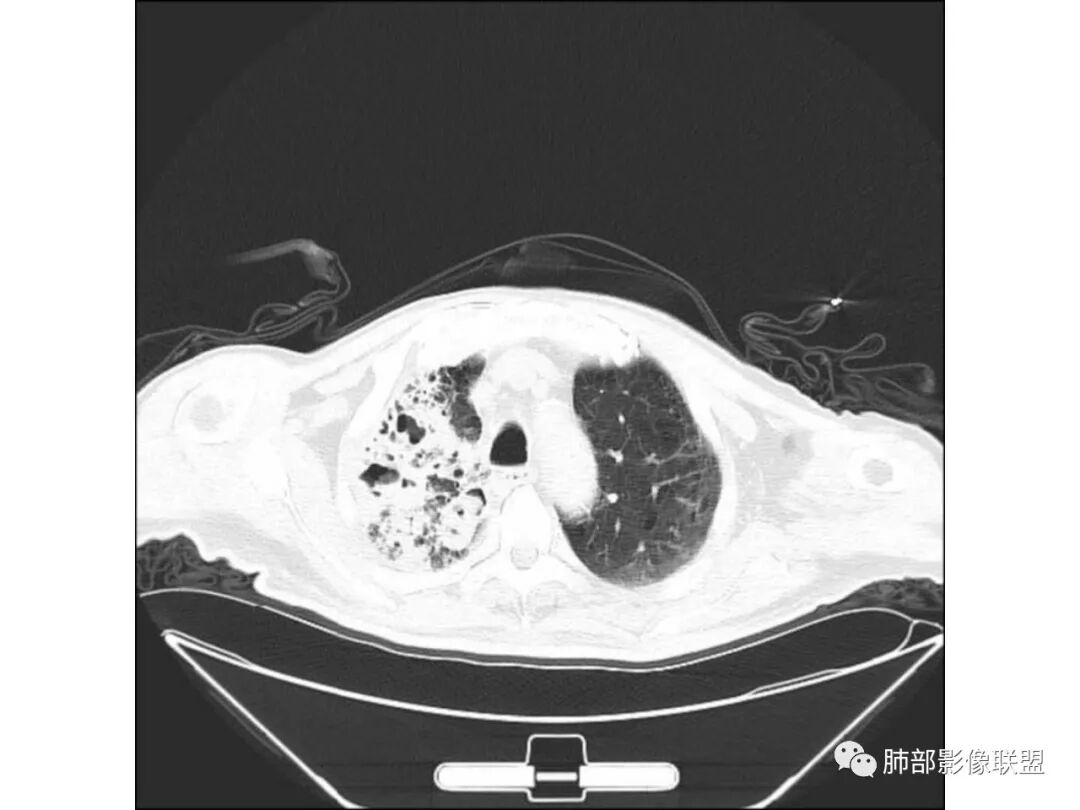

老年男性,糖尿病患者,右肺上叶大片状影伴多发小空洞和支气管充气征,有重力分布趋向,播散灶不明显,两肺胸膜下多发慢性炎症改变,有肺气肿肺大疱背景,肺门纵膈多发小淋巴结,少许钙化,急性起病,首先考虑感染性病变,1.气肿性肺炎?2.肺克?建议结合临床相关实验室检查,影像学角度常规治疗后复查除外粘液腺癌可能。右肺上叶一空洞内见结节影,考虑合并曲菌感染,干酪性肺炎可以,主要没有播散灶,结核待排吧

病灶内支气管扩张,迂曲变形,多发空洞,实性成分密度不均,其内可见小斑片状略低密度影,似呈铸形,有增强就更好了。病灶周围边缘相对清晰磨玻璃,有收缩。未见胸腔积液。把肺炎型肺癌放第一位,炎性病变放第二位。

双肺多发GG0,外周分布,略受重力影响,部分可见囊,右上贴壁实变、气柱征、无璧空洞,卫星灶不明确,有2DM,常规考虑:间质肺基础,合并TB>坏死性肺炎(肺克)>腺癌。非常规:如HIV+,可能存在PCP并TB,似乎有曲菌球

老年男性,糖尿病病史,慢性病程,右胸廓塌陷,右肺沿支气管分布实变及GGO,叶段分布趋势,其内见支气管充气征及虫蚀样空洞,周围间质受累,指向气道来源病变播散,纵隔淋巴结肿大,密度高伴钙化,综合考虑干酪性肺炎。鉴别肺炎型肺癌。

老年男性,有糖尿病史,右肺上叶大片实变影,有支气管充气征,支气管走行僵直,有扩张,有多发无壁小空洞和俩个稍大空洞,胸膜稍增厚,双下肺野间质性改变,考虑肺结核,干酪性肺炎可能性大。

老年男性,右肺上叶大片实变,边界局部清楚,局部模糊,其内见支气管充气征及多发大小不等的小泡状及分枝状无壁空洞。双肺下叶磨玻璃样间质性改变。综合考虑右肺上叶结核,干酪性肺炎可能。

老年男性,糖尿病患者,一般容易感染和结核。影像表现:右肺上叶大片状影伴多发小空洞和支气管充气征,有坠重感,小空洞内似见反晕,双肺胸膜下多发慢性炎症改变,右肺门纵膈多发小淋巴结。大致表现考虑良性感染性病变大于恶性肿瘤性病变。考虑1.结核2真菌感染性病变,3.肺克,4.粘液腺癌。建议结合临床相关实验室检查。

老年男性,糖尿病10年,咳嗽气喘10天,肺气肿背景,右上肺大片实变影,内见虫蚀样空洞及空气支气管征,局部可见新月形空洞影,支气管局部欠光整,考虑感染性病变,结核?其内合并曲霉可能。

有肺气肿背景,纵隔淋巴结钙化,肺部有纤维化,右肺大片实变,内有融合空洞,未见液平,支气管远端有扩张,部分近段狭窄截断,病灶周边树芽不明显,考虑结核可能大,鉴别腺癌,多为假大空,少有空洞,支气管远端少有扩张所以不符合,肺部感染,多有空洞液平,所以不符合。

老年男性,咳嗽气喘10天,双肺明显肺气肿,右上肺叶实变,内见大量空洞及囊腔样改变(部分为支气管扩张),实变区周围表现为网格样改变,有明显的小叶间隔增厚,边界似清非清,支气管走行僵硬,有枯树枝样改变,双下肺胸膜下小叶间隔增厚明显,边缘相对模糊,综合考虑如下:1、粘液腺癌可能大(枯树枝样改变,边界似清非清,小叶间隔增厚符合)。2、结核,右上肺似像干酷样改变,内有空洞及支扩样改变支持,但下肺及左肺无相关支气管播散的小叶中心结节及树芽,不支持,临床病症不支持,只有咳嗽,喘气,无咳痰及结核中毒症状。当然结核是妖,需要结合痰检及结核相关指标进一步明确。3、肺克,虽有10年糖尿病史,但肺部只有右肺改变明显,无胸膜下脓肿表现,无脓毒栓表现,临床症状也不支持。4、其他感染?双下肺胸膜下病灶边缘模糊,不完全除外,需要结合临床炎性指标分析。

右上肺大片状高密度影,呈蜂窝样改变,部分气腔无壁,部分呈厚壁改变,内部结构紊乱,部分边缘GGO边界清楚,大小不一,病灶近端小远端大,近端支气管壁增厚,支持感染性病变,考虑结核,其内支气管呈枯树枝改变,病灶局部膨隆,内部结构紊乱,边界的GGO部分清楚,恶性(腺癌)待排。